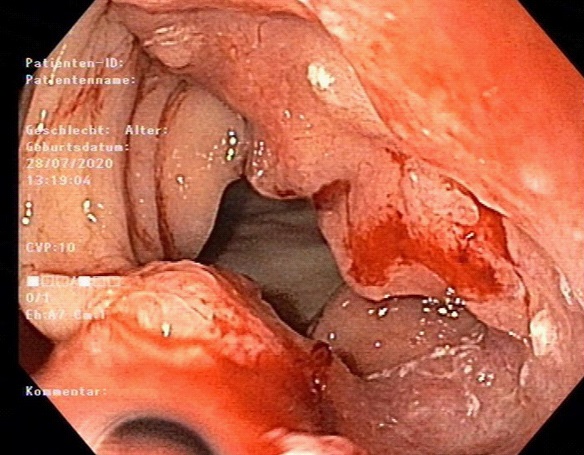

Figure 2: The photo of pathology of adenocarcinoma in the colon interposition (endoscopic biopsy).Blood tumour markers were normal (CEA 1,7 ng/ml, CA 19-9 9 U/l). Colonoscopy revealed no changes. By performing esophagogastroduodenoscopy (EGDS) we found a tumour stenosis in colon interportal (30 cm from incisor teeth, Figure 3).

Figure 3: Tumour stenosis in the colon interposition, esophagogastroduodenoscopy.

Because of tumour stage our multidisciplinary General Tumorboard advised the systemic treatment (Ardalan Protocol: 5-Floururacil 2600 mg/m² + Folinic acid 500 mg/m²). Before the chemotherapy initiation the patient was urgently admitted to the hospital because of atrial fibrillation episode and relevant 3-coronary arteries stenosis. The extra luminal percutaneous angioplasty was performed with 2 stents implantation. After the beginning of anticoagulant therapy the patient had an episode of gastrointestinal bleeding from the colon interportal, that required no surgical or endoscopic treatment. We could start the chemotherapy 10 weeks after the diagnostic VATS with a normal patient‘s tolerance. At the time of article writing the patient is clinically stable after 6 full cycles of chemotherapy, has no dysphagia and stable body weight. Actual computer tomogra . Actual computer tomography and EGDS control revealed no signs of tumour progression.